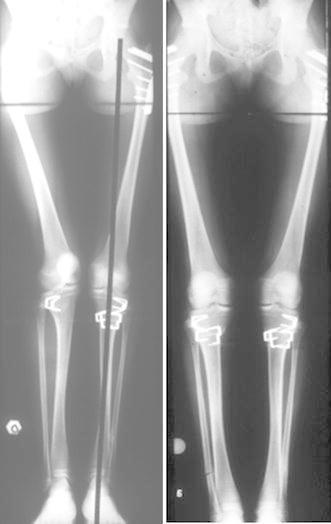

Torsión femoral / Femoral torsion

Torsión femoral*

Femoral torsion*

The upper end of the femur consists of the neck and head (the ball) articulating with the acetabulum (or cup) at the hip joint. The neck and head of the femur is pointed inwards with a slight forward inclination. This slight forward inclination is called femoral neck anteversion. The amount of femoral neck anteversion is 40 degrees at birth, and decreases with age to about 15 degrees at maturity. This is the normal evolutionary process of growth in most people. In some instances, the femoral neck anteversion present at birth does not decrease, but stays excessive compared to age, giving rise to the condtion of excessive femoral neck anteversion, or femoral torsion.

Torsión femoral anterior | Torsión femoral posterior | Torsión tibial Anterior femoral torsion | Posterior femoral torsion | Tibial torsion